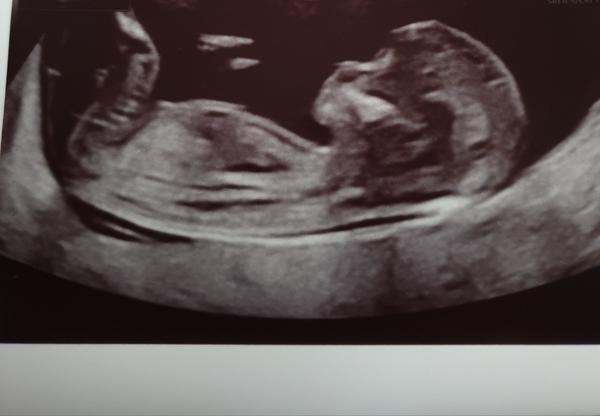

poznal byste pohlaví miminka?

Fotky jsou ze screeningu v trimestru a stáří miminka je 13+0.